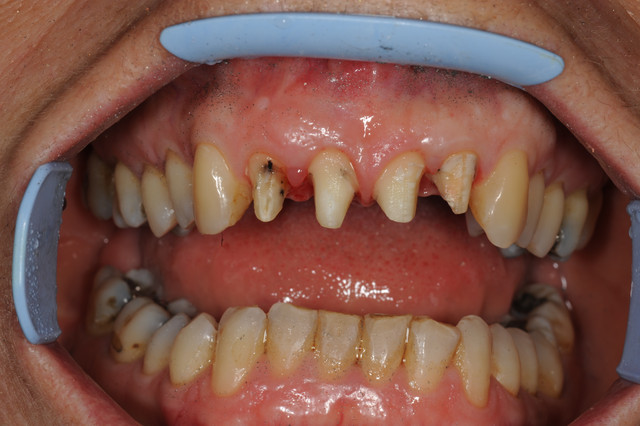

E.max crown try in 280713

#Togias 190713 nora